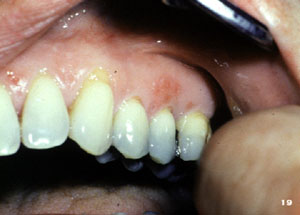

La mayoría de las lesiones de herpes recurrente involucra la piel y el borde del labio. Cuando se desarrolan en el interior de la boca las lesiones se limitan a la encía, como se muestra aquí. Un acúmulo muy pequeño y localizado de vesiculas.